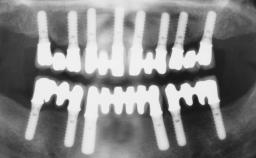

Conventional Loading of Six Implants in the Mandible and Final Restoration with a Full-Arch Metal-Ceramic FDP

# of Implants 6

Type of Implants One-Piece

Defining Characteristics Fully edentulous lower jaw to be rehabilitated with two or more implants

Modality > 4 implants, extending to mental nerve region

Bone Volume Horizontally and vertically sufficient

SAC Level Complex

Defining Characteristics Fully edentulous lower jaw to be rehabilitated with an implant-borne fixed dental prosthesis

Retention Screw-retained, with 4 or more splinted implants Screw-retained, with 4 or more splinted implants